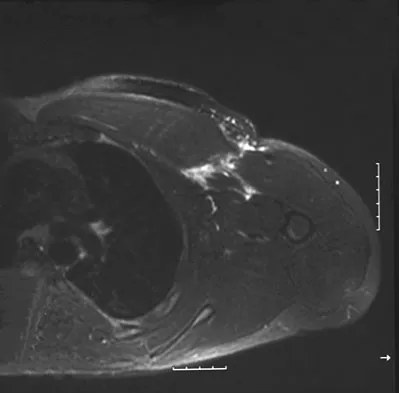

Figures 49a and 49b show MRI scans of the shoulder. What is the most likely diagnosis?

Explanation